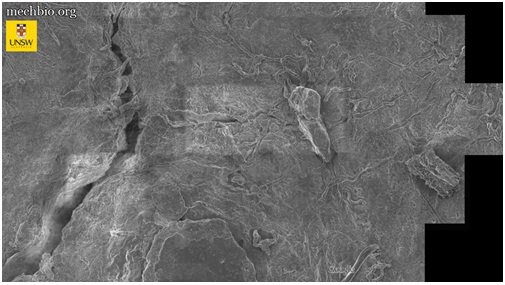

برای درک بهتر ترافیک سلولی در بدن انسان، تصاویر متعددی از استخوان لگن خاصره با استفاده از میکروسکوپ الکترونی روبشی تهیه شد؛ سپس این حجم عظیم از دادهها با استفاده از الگوریتمهای گوگل برای بزرگنمایی و کوچکنمایی بر روی بافت استفاده شد.

در حال حاضر از این فناوری برای مشاهده بافت لگن و درک بهتر آرتروز و دردهای مفصلی مزمن در افراد سالمند استفاده میشود، اما محققان امیدوارند از این فناوری در آینده نزدیک برای بررسی سایر بافتها نیز استفاده کنند.